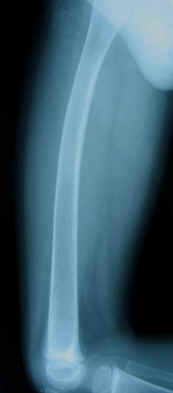

A plain x-ray of the left thigh revealed an antero-lateral

convex deformity of the left femoral shaft caused by malunion of

a fracture with poor callus formation, cortical bone atrophy and

osteoprosis, associated with osteolytic lesions (Fig. 1).

Osteoprosis of the right femur and spine was also found (Fig.